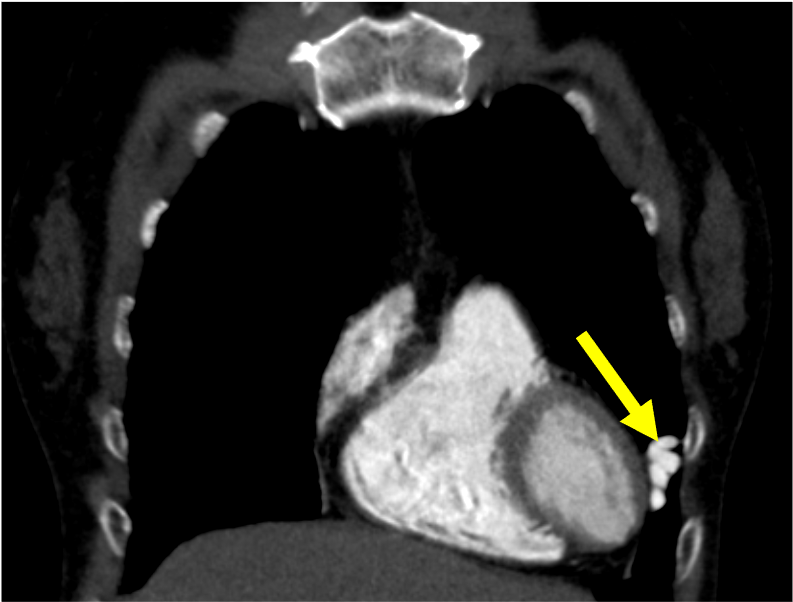

肺動静脈奇形は肺動脈・静脈が正常の毛細血管を介さずに短絡する血管奇形であり、肺動静脈瘻と呼ばれることもある。臨床症状としては低酸素血症や喀血、稀に血胸を示す。また、脳膿瘍や奇異性脳梗塞などの合併症を伴う可能性が知られている。しかし無症候性に肺結節として偶発的に指摘される例も少なくない。流入動脈、流出静脈がともに1本の場合をsimple type、複数の場合をcomplex typeと分類する。

造影CTでは肺動脈と同等の強い造影効果を呈し、単純CTに比して詳細な評価が可能となる。動静脈奇形の大きさ、流入動脈・流出静脈の数や吻合の位置をあらかじめ確認することで、治療計画に有用である。また、3D画像を再構成することでより立体的に形状を把握することができ、任意の方向から画像を観察することで塞栓時のアクセスルートを決定する一助となる。